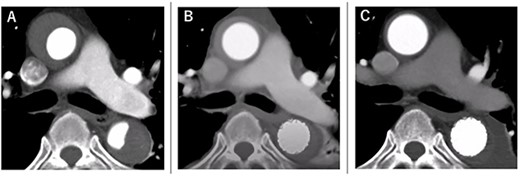

The postoperative course was uneventful, and he was discharged 14 days postoperatively. Rapid aortic remodeling was observed with eCT at 1 and 11 days postoperatively (Fig. 4). Right iliac artery dissection did not impede blood flow and no other complications such as stent-induced new entry (SINE) were observed (Fig. 5). We strictly followed up the false lumen and iliac dissection.

The course of aortic remodeling at the ascending aorta. (A): Preoperative, (B): 1-day postoperatively, (C): 11-day postoperatively (see Video 1).